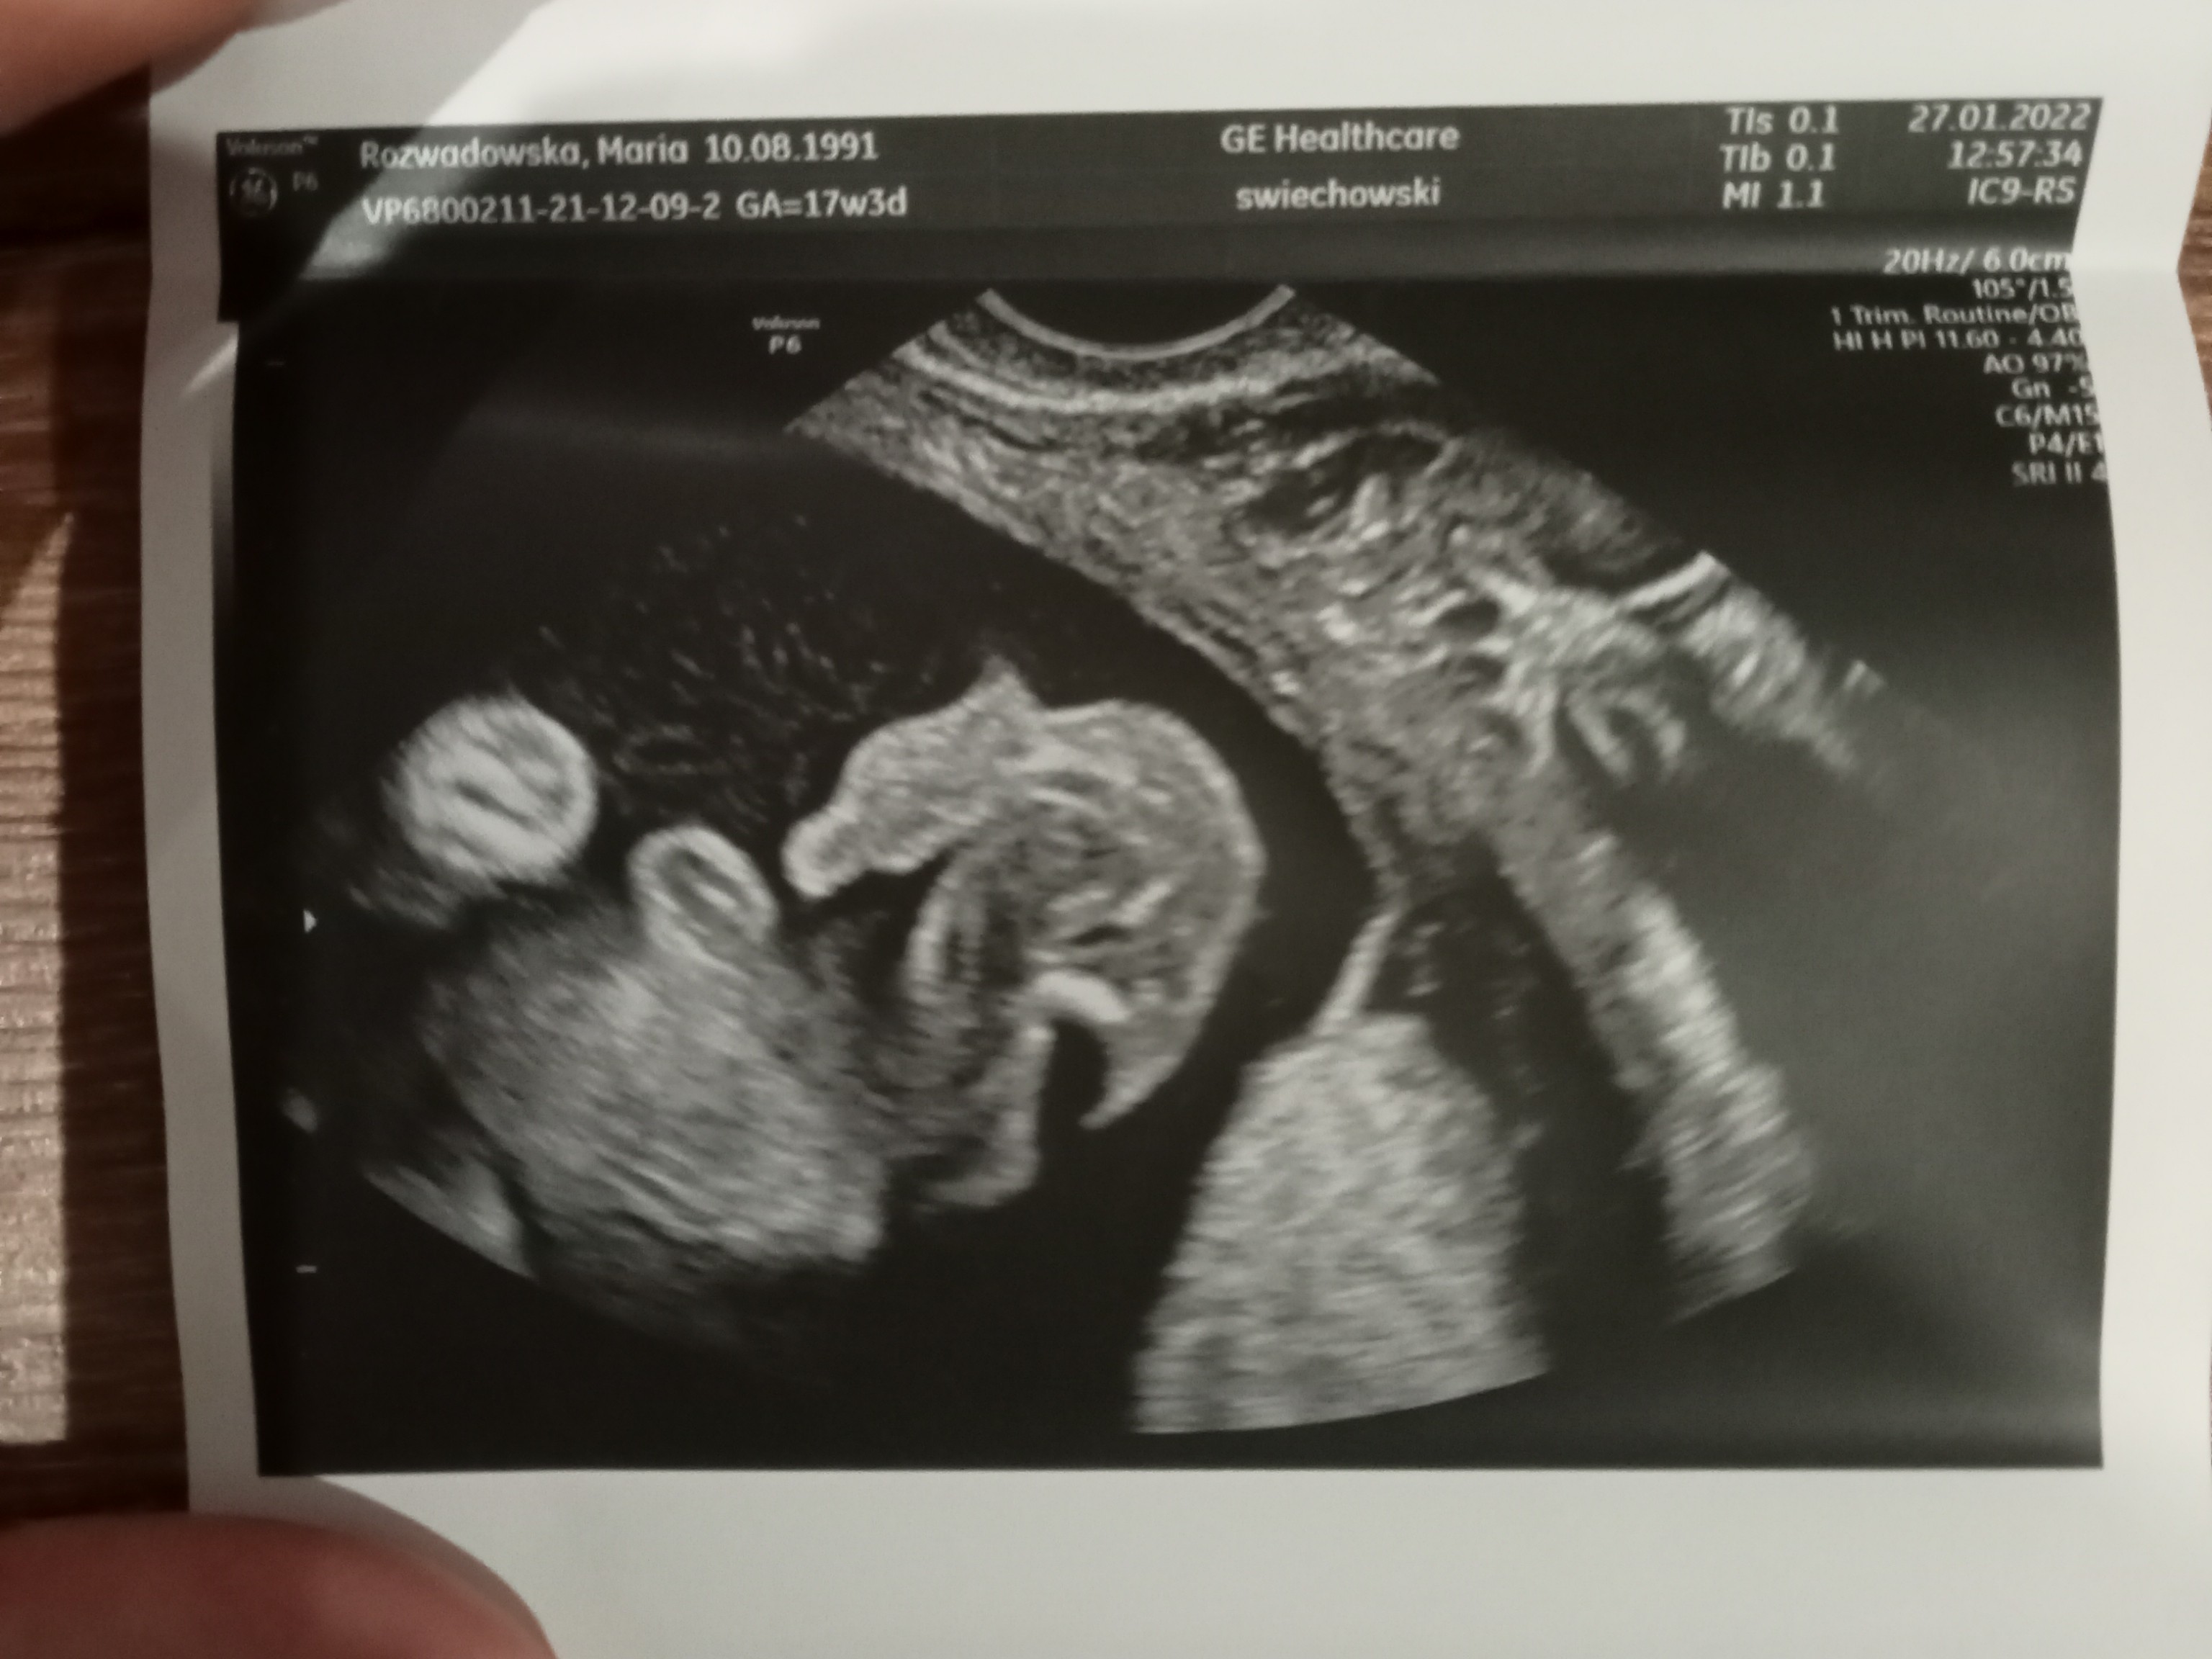

Siusiak czy pępowina?

Hej, w 12 tyg ciąży na prenatalnych sugerowano mi, że to dziewczynka, natomiast przy kolejnym usg w 18 tyg lekarz prowadząca powiedziała, że chłopiec. Co myślicie?

W 16 , że chłopak też widziałam siusiaka, a w 20 ponownie że dziewczynka , połówkowe to potwierdzały( więc tamten siusiak był pępowiną) za niedługo będziesz miała połówkowe więc poproś o 4d będziesz miała pewność ☺️☺️